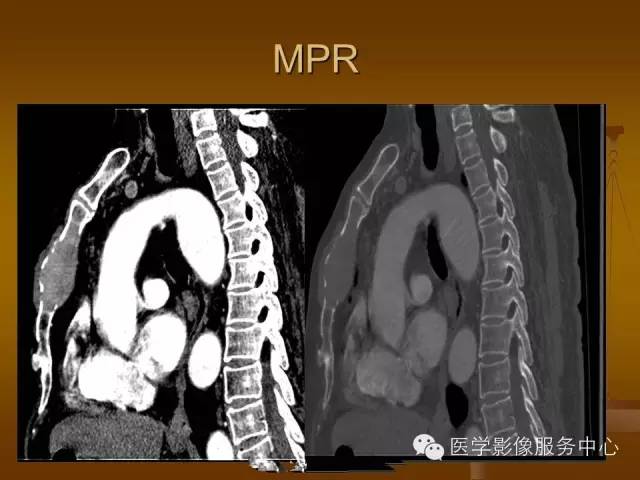

胸骨浆细胞骨髓瘤1例CT影像表现

特征性穿凿状、鼠咬状及蜂窝状骨质破坏,边缘清楚,骨质疏松,病理性骨折及软组织肿块等表现,骨质硬化及骨膜反应少见。

骨质破坏区完全为软组织取代,骨质膨胀,边界清楚,常突破骨皮质形成软组织肿块。

增强扫描可见病灶轻中度强化,一般于静脉期达峰值。